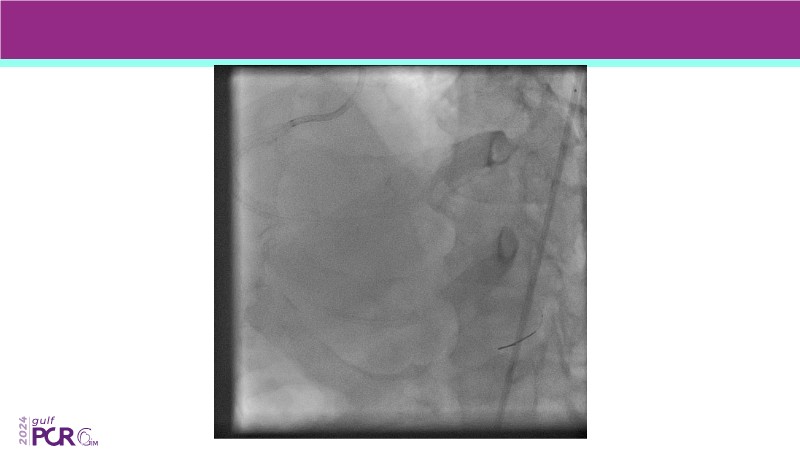

Explore the future of complex PCI with Meril Life’s advanced solutions. Learn about thin-strut platforms, dedicated stents for side branches and diffuse lesions, the role of drug-eluting balloons in metal-free PCI, and the clinical potential of the Myval THV technology.

- To learn about the novel Myval THV technology, its key features, procedural and clinical benefits and learn about the clinical data in a vast cohort of patient population